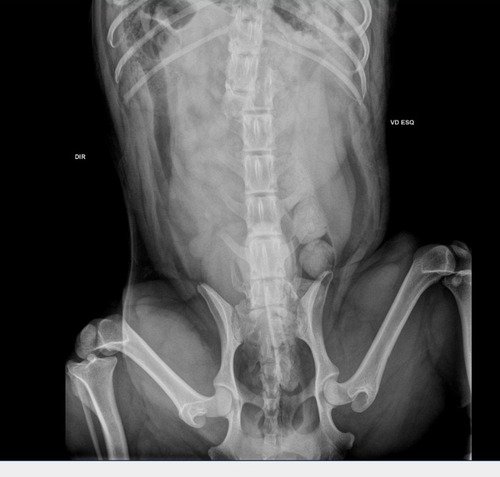

Meu nome e Fernanda,sou tutora do snoop,meu doguinho foi atropelado,quebrou a coluna e precisou passar por uma cirurgia só as despesas com o hospital já estão em $8,636,00 ,ele recebendo alta precisamos comprar remédios,e começar o quanto antes a fisioterapia para que ele tenha qualquer chance de voltar a andar,